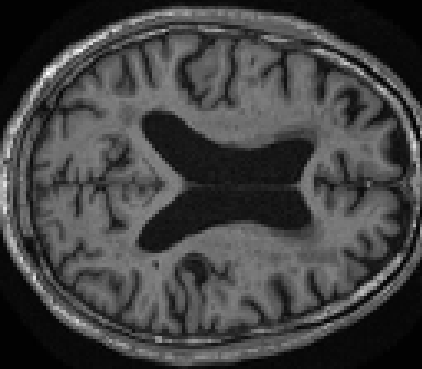

Looking at sample synthetic PET images in Fig. 3, it can be seen that all of the models are able to make reasonable predictions. The outputs of the U-PET and U-PET (no att.) look very similar and are smoothed compared to the input. The pix2pix predicts more details, which seem to be important for the discriminator. However, even though this model has finer predictions, the intensity values are worse compared to the U-PET and U-PET (no att.) as seen in Fig. 2; an example is given in Fig. 3 in the second row.

From a clinical perspective, the synthetic generated PET show a smoother version of the real PET images but keep the same pattern of FDG uptake, especially, hypometabolism in the respective brain areas. This backs up our hypothesis, that MRI contains information that correlates with the functional information of PET images. Moreover, the synthetic PET could be used as complementary visualization for physicians beyond the task of classification.

In Fig. 4, the attention maps of the U-PET are shown for multiple examples. On the one hand, the attention map of the skip connection (AttMap skip) highlights details of the brain structure, which is in agreement with the assumption that the network has to transform the specific structures of the MRI scan into the PET modality. On the other hand, the attention gates used for the classification task rather focus on more specific regions. One can observe a trend that the attention maps used for classification tend to highlight regions which have a low uptake in the PET. Since areas with a lower uptake in the PET correspond to areas with lower functional activity (hypometabolism), this focus area of the network seems reasonable with respect to the classification task.